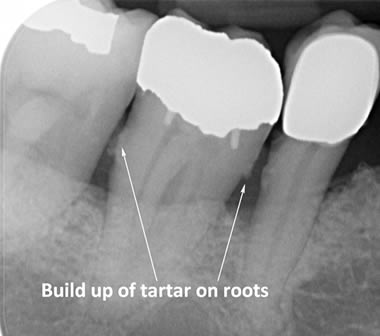

The diagrams below show the different stages of gum disease

Calculus (tartar) is the hard deposit which forms on the teeth in areas where plaque is left undisturbed. Calculus is too hard to brush off with a toothbrush and needs to be removed by the Dental Hygienist with special scaling instruments.

In cases of advanced gum disease our Hygienist’s will also carry out deep scaling which cleans the root surfaces beneath the gum level. When pockets develop in the gums around the teeth plaque bacteria and calculus form on the root surfaces of the teeth and are protected from toothbrushing by the overlying gum. However, our Hygienist’s have special thin scaling instruments which can go down inside the pockets to clean the root surfaces. This treatment is carried out in small sections under local anaesthetic to ensure that you are comfortable throughout the treatment.